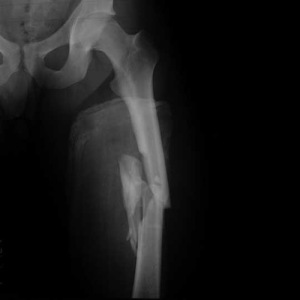

Врачи отмечают, что перелом диафиза бедренной кости часто сопровождается сильной болью, отеком и ограничением подвижности. Основными симптомами являются деформация конечности, укорочение ноги и невозможность опоры на поврежденную ногу. Для диагностики используются рентгенографические исследования, которые позволяют точно определить тип и степень перелома. Лечение может варьироваться в зависимости от характера повреждения: в некоторых случаях достаточно консервативной терапии с использованием гипса, в других — требуется хирургическое вмешательство, например, остеосинтез. Врачи подчеркивают важность ранней реабилитации, которая включает физиотерапию и лечебную физкультуру, что способствует восстановлению функции конечности и предотвращению осложнений.

Клиническая картина и диагностика

Так как при переломах диафиза бедренной кости часто происходят разрывы и ушибы тканей, наблюдается увеличение объема бедра. Это происходит из-за возникновения травматического отека. У пострадавшего может развиться болевой шок. Это объяснятся сильными болевыми раздражениями и большой кровопотерей, к которой приводит кровоизлияние в ткани. Если у потерпевшего развился шок, очень важно вывести его из этого состояния.

Смещение, как мы уже разобрали, может быть самым разным. Это может определять положение ноги. Чаще всего поврежденная конечность не может активно функционировать. Человек не способен ходить. Конечность перестает выдерживать даже малейшую нагрузку. В большинстве случаев нога укорочена и деформирована. Пострадавший принимает вынужденное положение на спине. При смещении отломков могут повредиться крупные сосуды. Риск такого состояния особенно велик при переломе в нижней трети, при котором периферический отломок при смещении может повредить подколенную артерию, что приводит к сильному кровотечению.